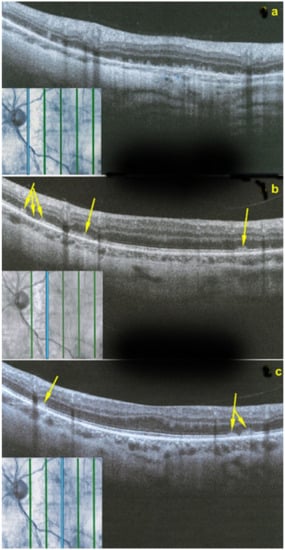

However, these typical lesions are not always clearly visible on fundoscopy while they are seen more precisely when using the near infrared reflectance (NIR-R) imaging mode that demonstrates sharply demarcated, hyporeflective lesions more definite than those found on fundoscopy [78]. Blue-light fundus autofluorescence (488 nm, lipofuscin related) (BAF), fluorescein angiography (FA) and indocyanine green angiography (ICGA) are usually not significant, while near infrared autofluorescence (787 nm, melanin related) (NIR-FAF) can show abnormalities [78]. Together with the NIR-R, the spectral-domain optical coherence tomography (SD-OCT) represents a very useful new imaging technology to diagnose AMN demonstrating that the outer retina is primarily affected. In the early phase of the disease, OCT shows a transient, localized hyperreflectivity at the outer plexiform layer (OPL)/outer nuclear layer (ONL) [79] (Figure 30). In a short time, the hyperreflectivity is replaced by focal abnormalities of the ellipsoid zone (EZ) and interdigitation zone (IZ) that are often associated with thinning of the ONL (Figure 31 and Figure 32) In addition, electrophysiologic analysis also with multifocal electroretinography has clearly localized the lesion impact at the level of the outer retina [80]. AMN has good prognosis with a slow, progressive improvement of the symptomatology. Macular lesions can persist for a long time.